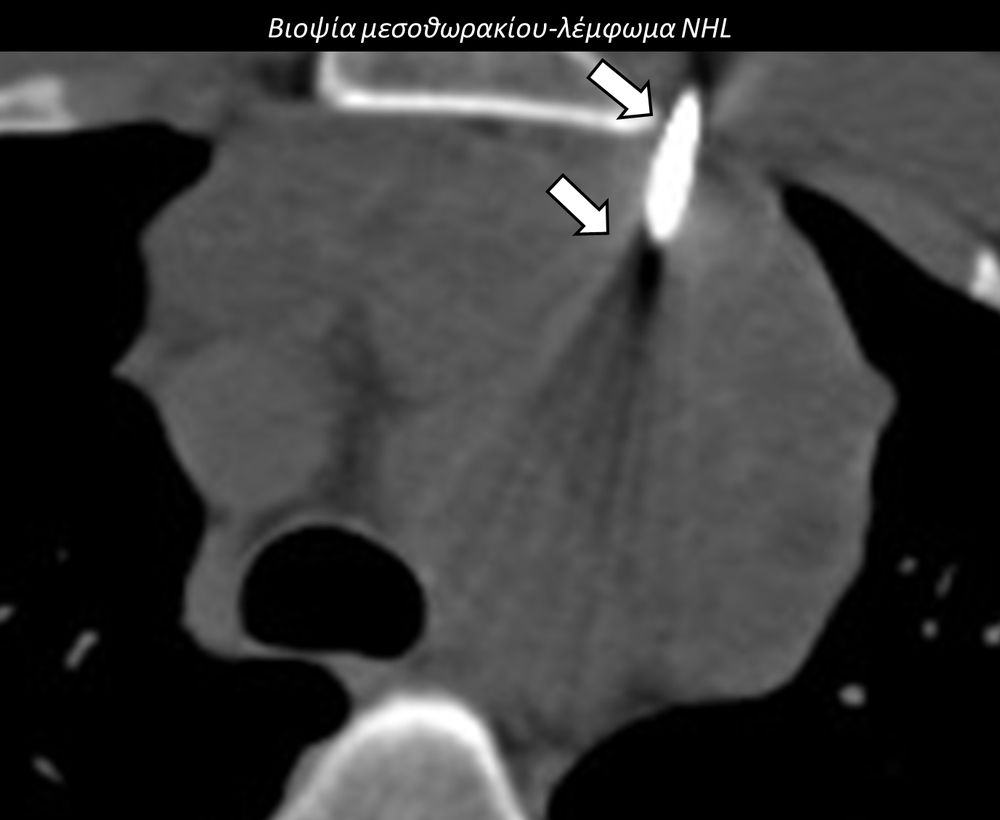

Η διαδερμική βιοψία είναι μία ελάχιστα επεμβατική μέθοδος λήψης υλικού από τον όγκο για κυτταρολογική και ιστολογική εξέταση, από εστιακές αλλοιώσεις του ήπατος, πνεύμονα, νεφρού κλπ. Συστήνεται από τον κλινικό ιατρό ανάλογα με το είδος και το μέγεθος της βλάβης και πραγματοποιείται με ασφάλεια από επεμβατικό ακτινολόγο με την καθοδήγηση αξονικού τομογράφου ή υπερήχων. Στη σύγχρονη ογκολογική θεραπεία όπου γίνεται προσπάθεια καταπολέμησης του καρκίνου σε μοριακό επίπεδο κρίνεται αναγκαία η ακριβής ιστολογική ταυτοποίηση του όγκου ώστε να εφαρμοσθεί εξατομικευμένη θεραπεία για το βέλτιστο αποτέλεσμα. Οι κατευθυνόμενες βιοψίες στοχευουν στο να παρέχουν στον κλινικό ογκολόγο το απαραίτο ιστοπαθολογικό υλικό που θα του επιτρέψει να εφαρμόσει την κατάλληλη θεραπεία για τον ογκολογικό ασθενή.